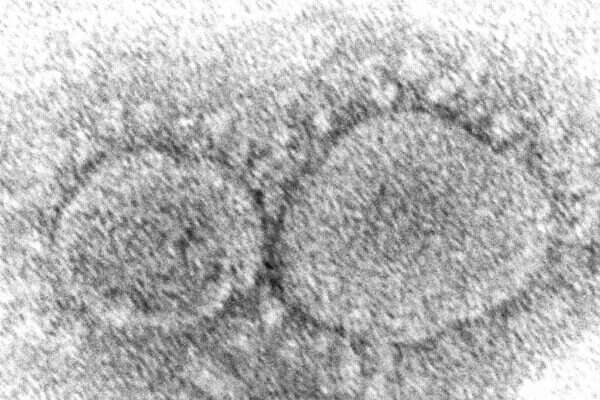

וריאנט חדש של נגיף הקורונה אותר על ידי חוקרים בדרום צרפת, לאחר ש-12 מקרים שלו נתגלו בקרב נוסעים ששבו למדינה מקמרון שבמערב אפריקה.

לווריאנט החדש, שזכה לשם B.1.640.2, יש 46 מוטציות ו-37 מחיקות גנטיות, דבר שגורם לחוקרים לחשוש כי הוא מדבק ברמה גבוהה מאוד, ואולי אף מסוגל להתגבר על נוגדנים שנובעים מחיסון והחלמה ממחלת הקורונה. הזן התגלה על ידי המכון לחקר מחלות מדבקות באגן הים התיכון בצרפת במהלך חודש דצמבר. הכינוי שהוצמד לזן החדש הוא שמו של מכון המחקר שגילה אותו, IHU.